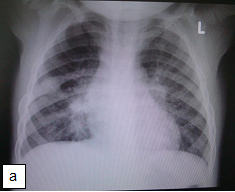

Presentation: The signs and symptoms of CMV disease often overlap with other infectious processes, therefore, the diagnosis of CMV disease in HIV-infected children should take into consideration clinical presentation and radiological finding along with laboratory testing. CMV pneumonia presents with fever, dyspnoea and hypoxemia. A chest radiograph shows diffuse pulmonary infiltrates (ground glass appearance) as seen in other viral pneumonias and PCP. The isolation of CMV from isolates including BAL does not prove that the child has CMV pneumonia. Co-infection with both PCP and CMV is common.